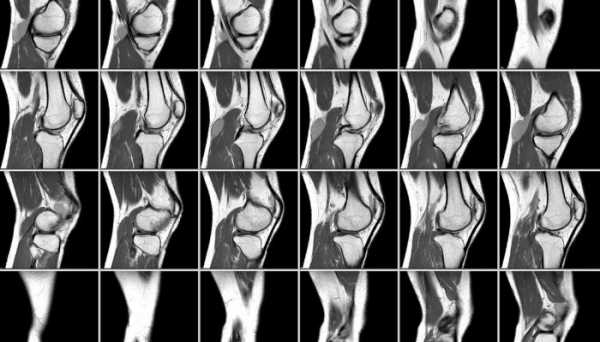

При неприятных ощущениях в колени, врач делает тщательный осмотр и диагностику:

- МРТ.

- Рентген.

- Ультразвук.

- Денситрометрию.

- Пункцию.

- Биопсию.

- Микробиологические исследования.

- Серологический анализ.

- Общий анализ крови, мочи.

Чтобы делать окончательные выводы о том, что стало причиной появления щелчков в колене, следует обратиться к дополнительным методам диагностики. Они включают не только инструментальные, но и лабораторные методики, позволяющие установить происхождение симптомов. Чаще всего рекомендуют пройти такое обследование:

- Клинические анализы крови и мочи.

- Биохимическое исследование крови (мочевая кислота, кальций, ревмопробы, острофазовые показатели).

- Анализ синовиальной жидкости.

- Рентгенография суставов.

- УЗИ колена.

- Магнитно-резонансная томография.